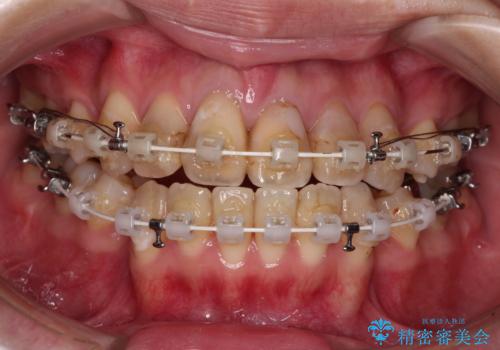

- 矯正装置

- 審美装置

口元の突出感はありませんが、前歯の重なりが著しいため、目立ちにくい表側のワイヤー装置にて、上下左右の第一小臼歯4本を抜歯して矯正治療を行うこととしました。